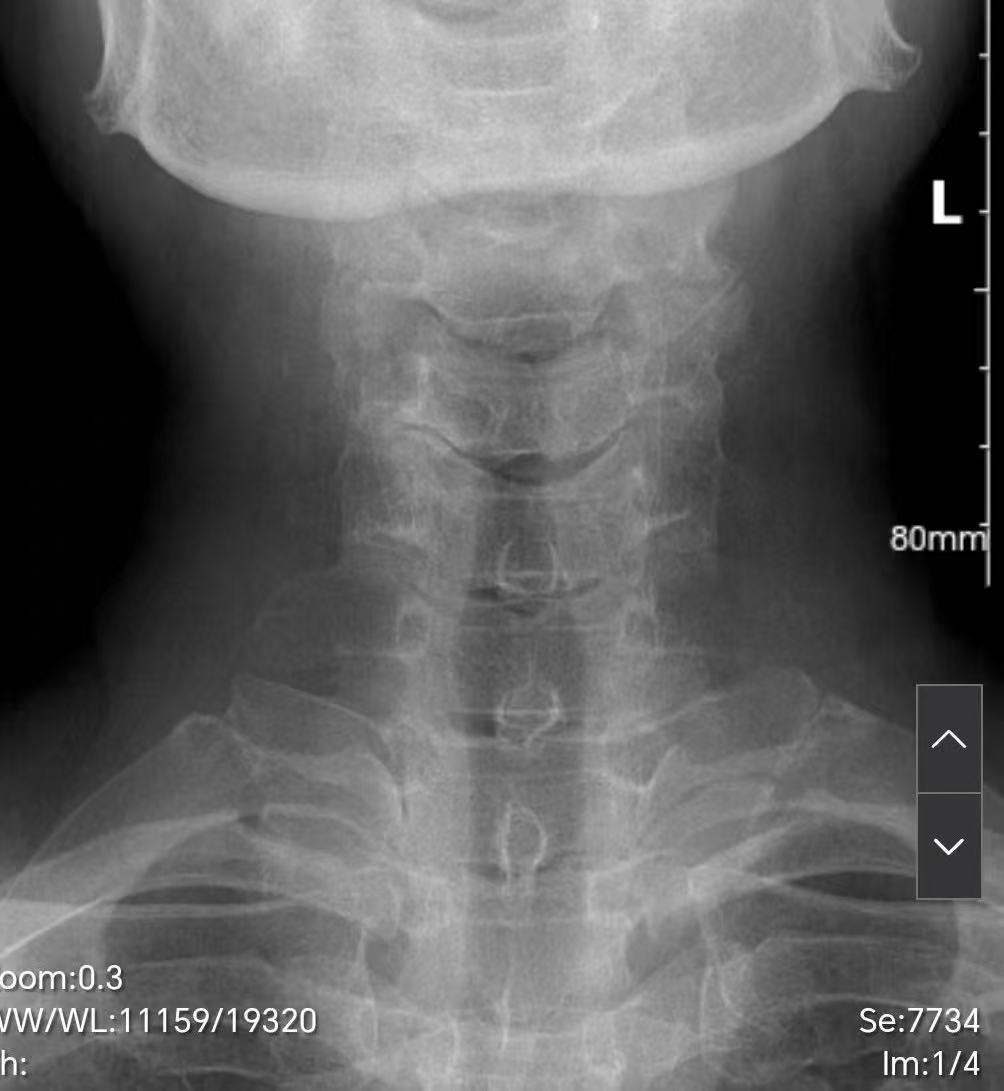

来自赫章县的61岁女性患者,因右上肢前臂持续性放射性疼痛、麻木到浙毕医院就诊。经完善相关检查,患者影像学检查明确:颈5/6、颈6/7椎间盘突出伴钩锥关节重度增生,脊髓受压并出现T2加权像高信号改变,神经功能已濒临不可逆损伤;其中颈5/6节段钩锥关节骨赘直接压迫右侧神经根,是症状的核心诱因。

术前,从CT上可见颈56右侧的钩椎关节明显增生、狭窄。磁共振上可见颈、颈 56、颈67 椎间盘突出,脊髓受压,脊髓信号改变R

术后,从X 和 CT 上可见,完整切除了颈56右侧钩椎关节。从磁共振可见,颈56、颈 67脊髓受压解除